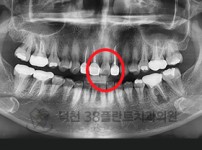

치료전후